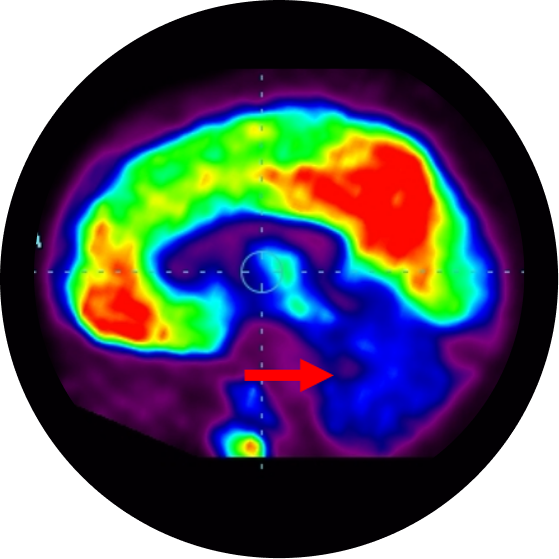

In autism, though the brain structure looks normal, there are functional abnormalities in specific regions of brain. This information, about the functioning of brain areas can be obtained from functional neuroimaging techniques like PET-CT scan and functional MRI scan of the brain. These imaging studies permit the study of the abnormal pattern of cortical activation in autism. These studies indicate that certain areas of the brain show reduced functioning like mesial temporal lobe (innermost part of the brain responsible for learning, understanding, memory, social interaction and abstract thinking), frontal lobe (the front part of the brain responsible for emotions and aggression) and cerebellum (responsible for balance, coordination, muscle tone and speech). Hence the dysfunction of these areas are responsible for problems seen in autism.

Positron Emission Tomography  Computed Tomography Scans showing areas of brain with reduced function

Medial Temporal Cortex

Cerebellum